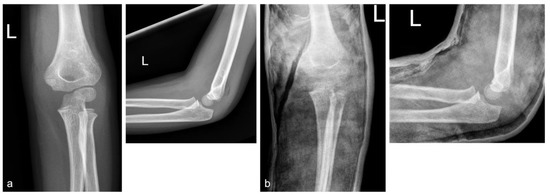

The Limited Significance of the Internal Rotation Stress Test in Pediatric Gartland Type III Supracondylar Humerus Fractures

Background: Gartland type III pediatric supracondylar humerus fractures can be unstable and prone to loss of reduction. The Internal Rotational Stress Test (IRST) aims to assess and address rotational instability during surgery. Method: This retrospective study analyzed treatments for Gartland type III pediatric [...] Read more.

Background: Gartland type III pediatric supracondylar humerus fractures can be unstable and prone to loss of reduction. The Internal Rotational Stress Test (IRST) aims to assess and address rotational instability during surgery. Method: This retrospective study analyzed treatments for Gartland type III pediatric supracondylar humerus fractures at our institution from January 2020 to December 2022. Only patients who underwent IRST were included. IRST was performed after inserting either two or three lateral pins. Patients were divided into Group 1 (IRST +) or 2 (IRST −) based on IRST results. Radiographic and clinical outcomes were compared between the two groups. Result: A total of 46 patients were included in the study. The mean age at the time of diagnosis was 5.7 years (range, 4 to 11 years), and the mean duration of follow-up was 2.8 years (range, 1.0 to 4.8 years). Group 1 consisted of 24 patients, and Group 2 comprised 22 patients. We did not find any differences in radiographic parameters and clinical scores between the two groups. Additionally, in both groups, there were no instances of major loss of reduction, defined as greater than 12 degrees or 12%. In five patients, we identified two types of fracture patterns that were stable with only two lateral pins. Conclusions: In patients with Gartland type III supracondylar humerus fractures, if reduction is adequately achieved and sufficient fixation force is maintained, the IRST results do not significantly impact radiologic and clinical outcomes. The pattern of the fracture can influence instability, necessitating further research on this matter. Full article